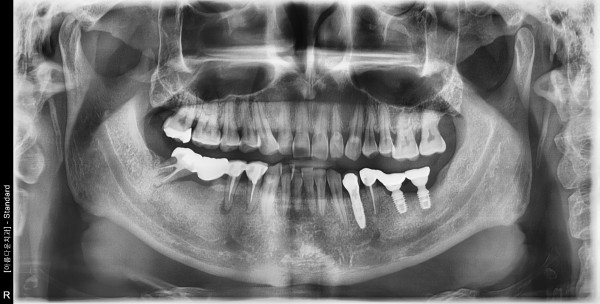

60대 남성 임플란트 식립